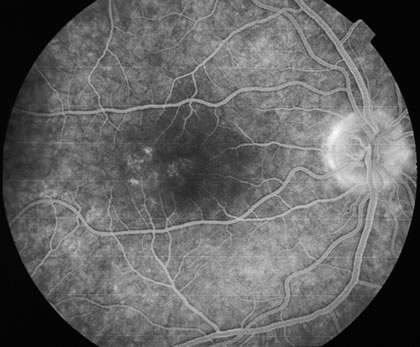

Determining whether the choroiditis has been caused by tuberculosis is sometimes very difficult. A chest x-ray may show evidence of an enlarged mediastinum as well as active pulmonary infiltrates or previous pulmonary scarring. Unfortunately, these are indirect evidence of ocular involvement or even that the disease is caused by tuberculosis. Sarcoidosis, histoplasmosis, and coccidiodomycosis can all give similar roentgenologic findings and somewhat similar fundus findings (Fig. 12).56 A long, thin, conjunctival biopsy measuring approximately 3 × 10 mm that is then sectioned in a breadloaf fashion can sometimes diagnose the presence of sarcoidosis.53 Mediastinoscopy or bronchoscopy can be used to determine the cause of the infiltrations. A purified protein derivative test (PPD) is done to see if there is a delayed hypersensitivity reaction indicative of exposure to tuberculosis. The PPD test may be positive in the absence of active tuberculosis. Unfortunately, outside the United States, bacille Calmette-Guérin (BCG) vaccine is given to try to decrease the incidence of tuberculosis. BCG can produce a false-positive PPD test. The polymerase chain reaction tests for tuberculosis are improving and can be considered if there is evidence that the laboratory where it will be performed has substantial experience in running this test. Vitreous or aqueous samples may be used if there is evidence of a vitreitis. In some cases a chorioretinal biopsy may be performed with the sample sent for tuberculosis culture, histopathology, and polymerase chain reaction.57 A response to antitubercular medications helps to make the diagnosis.58

Fig. 12. Multiple peripheral choroidal scars in an elderly patient with sarcoid uveitis. Note the resemblance to multifocal choroditis and also it can resemble intraocular lymphoma.